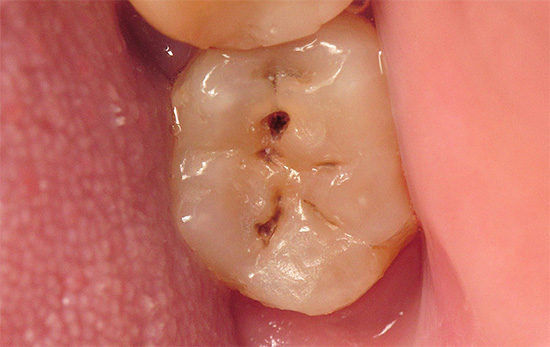

La fotografia sotto mostra un esempio di una cavità già formata durante il trattamento della carie profonda:

Le fasi principali del trattamento della cavità cariata con carie profonde sono:

- aprendo la cavità e rimuovendo i bordi sporgenti dello smalto

- pulizia manuale o automatica di tessuti ammorbiditi e infetti

- formazione di cavità per il materiale che verrà utilizzato per il riempimento permanente

- trattamento farmacologico della cavità formata con soluzioni deboli di antisettici (ad esempio, clorexidina al 2%)

- riempimento con materiale preselezionato.